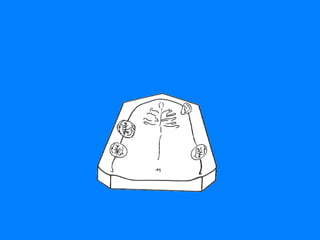

CLASE I DE KENNEDY RESTAURACION DENTO-MUCOSOPORTADA LIMITACION 36-44 La disminución del soporte mucoso, hace que los dientes pilares asuman un papel protagónico en las funciones de S.E.R.

CLASE I RESTAURACION MUCO-DENTO SOPORTADA LIMITACION 13-23 RESTAURACION  MUCO- DENTO SOPORTADA

CLASE I LIMITACION 33-43 RESTAURACION   MUCO- DENTO SOPORTADA